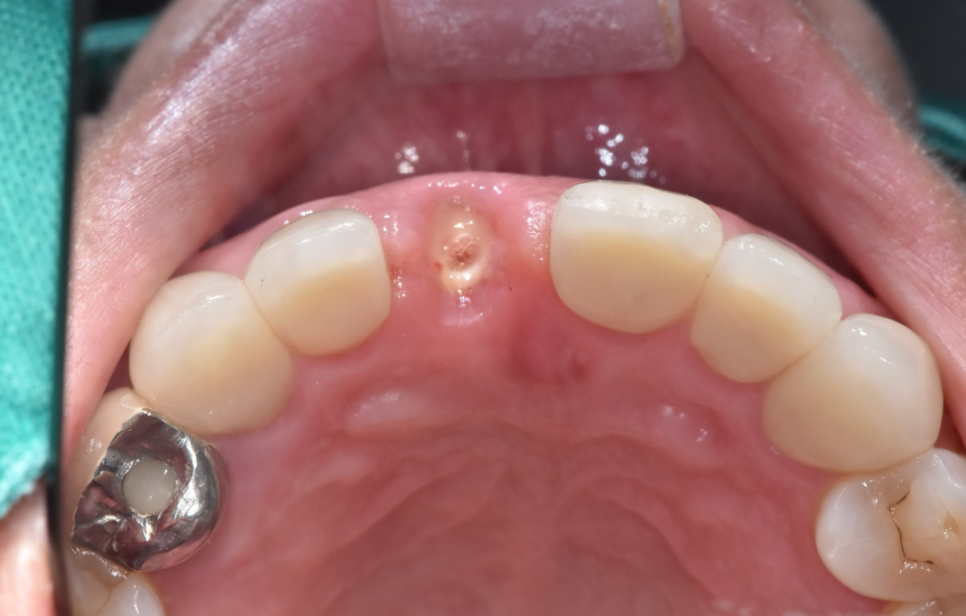

두번째 앞니가 비었을 때

앞니의 경우 빈 공간이 신경이 많이 쓰이실겁니다.

사회생활을 할 수 없다 하실 정도로...

240628

어떤 분은 치아가 없어서 맹구같다 표현해주셨어요ㅠㅠ

마스크로 가리고

손으로 가려도 식사할 때는 들통나기 마련입니다.

아무래도 자연 치아 사이에 플리퍼를 끼워드리면

티가 나긴 합니다.

그렇지만 아무것도 없는 것보다는 좋기에

앞니 임플란트 치료 시 만들어 드려요!